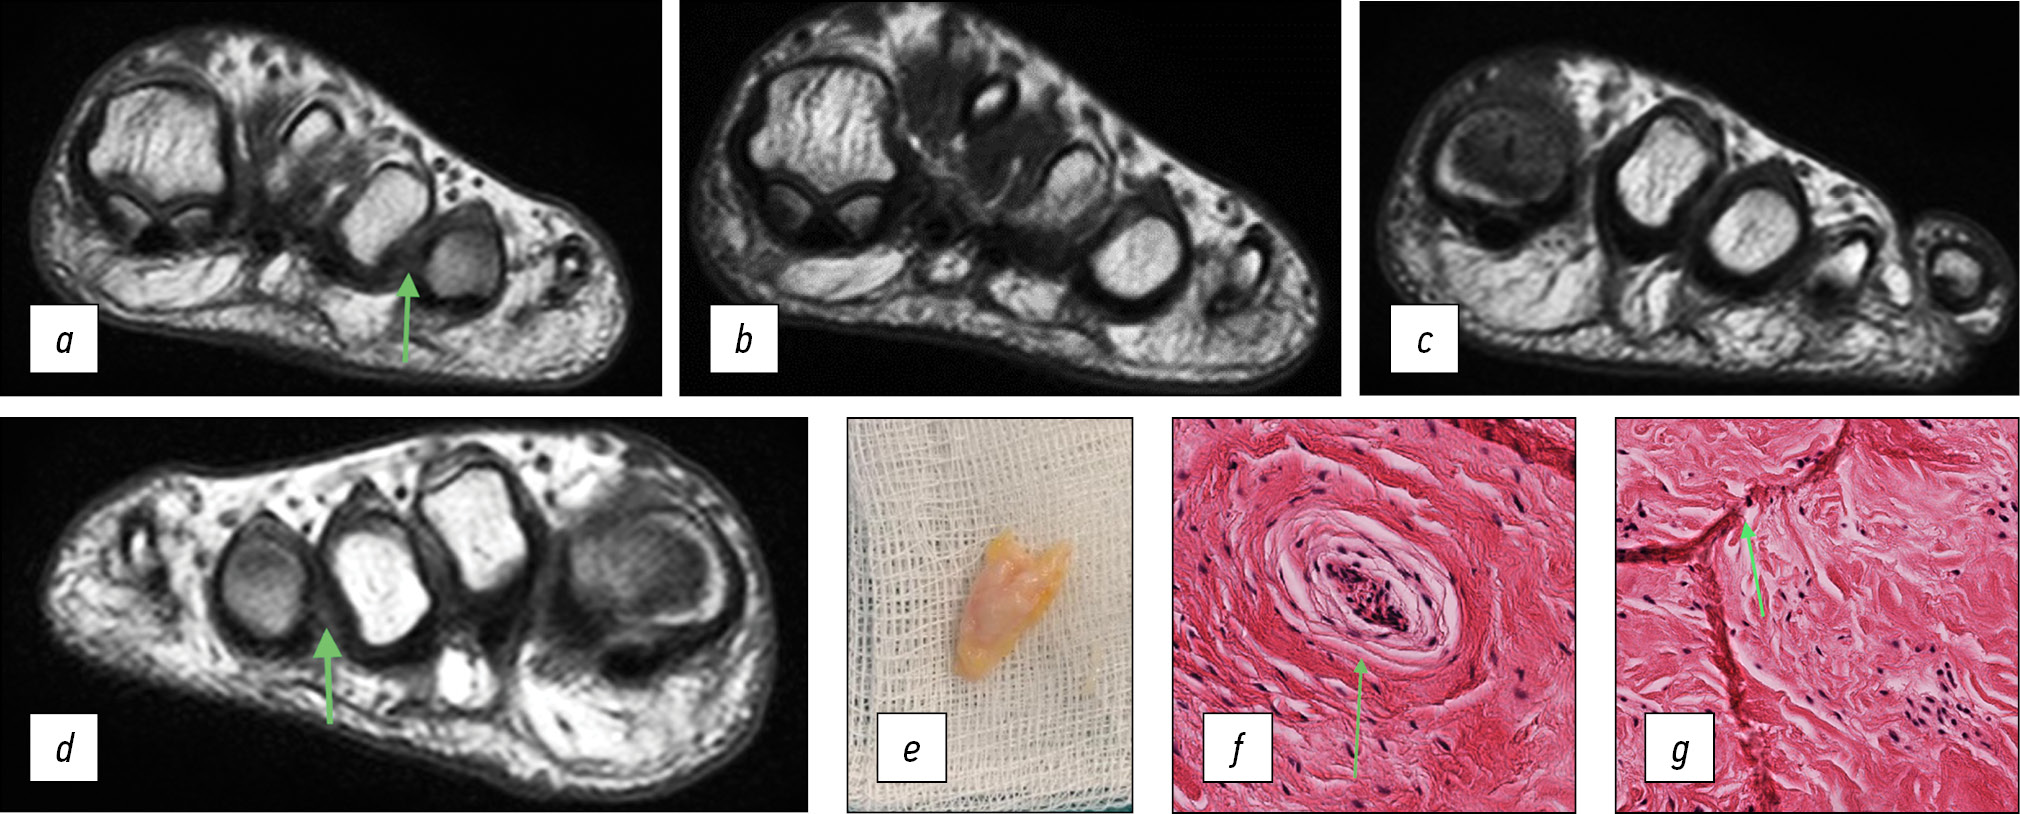

На полученных нами МР-последовательностях на уровне головок третьей и четвёртой плюсневых костей неврома третьего межпальцевого промежутка видна и без контрастного усиления на Т1- и Т2-взвешенных последовательностях (рис. 1a–c). При контрастном усилении полученный смешанный сигнал (рис. 1d) свидетельствует об отёке оболочки нерва и умеренно выраженном бурсите, что напрямую коррелирует с клинической картиной и длительным анамнезом заболевания.

Рис. 1. Пациент К., магнитно-резонансная томография: a — гипоинтенсивный сигнал по сравнению с окружающими тканями при Т1-взвешенной последовательности, неврома третьего межпальцевого промежутка; b — гипоинтенсивный сигнал по сравнению с окружающими тканями при Т2-взвешенной последовательности, неврома третьего межпальцевого промежутка; c — участок гипоинтенсивный сигнала при Т2-взвешенной последовательности (бурсит), срез, следующий за изображением b в дистальном направлении; d — смешанный гипо- и гиперинтенсивный сигнал (участок затемнения — отёчная оболочка нерва, окружающий гипоинтенсивный сигнал периневральный фиброз). Режим Т1 FS после введения контраста

Fig. 1. Patient K., MRI image: a — hypointensive signal compared to surrounding tissues with a T1-weighted sequence, neuroma of the third interdigital space; b — hypointensive signal compared to surrounding tissues with a T2-weighted sequence, neuroma of the third interdigital space; c — area of hyperintense signal on T2-weighted sequence (bursitis), the distal direction from image b; d — mixed hypo- and hyperintense signal (shaded area — edematous nerve sheath, perineural fibrosis surrounding the hypointense signal). T1 FS mode after contrast